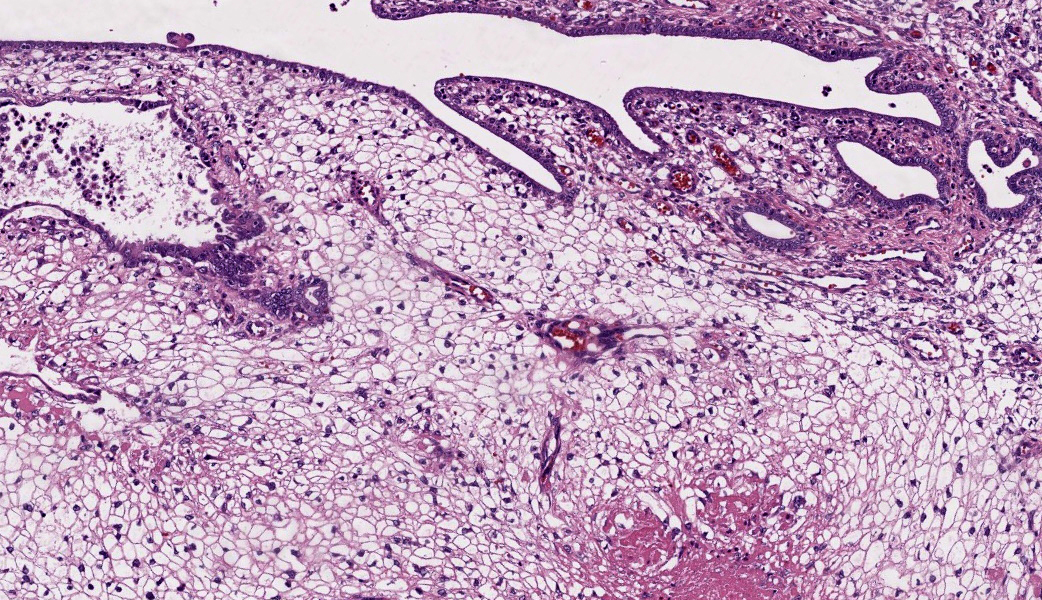

The endometrium on the mesometrial side of the uterus proliferated with the formation of large nodules and numerous polyps. The surface of the nodules and polyps was covered by endometrial epithelium, however, approximately 50% of the epithelium were eroded. The polyps and nodule contained numerous blood vessels with normal endothelium, along with cells that resembled large-vacuolated decidual cells, arranged in sheets. The decidual cells had distinct cell boundaries, a round shape, abundant transparent cytoplasm, and nuclei ranging from oval to irregular shapes. Mitotic figures were also occasionally observed. Just beneath the endometrial epithelium, the decidual cells exhibited a spindle-shaped morphology. (Fig.1 and 2)On the antimesometrial side of the uterine, endometrial hyperplasia was mild, decidual cells in the endometrial stroma were sparse, and proliferation of huge giant cells resembling trophoblast was prominent. The huge giant cells displayed a variety of morphologies, including round, spindle, to pleomorphic, with notably large, highly atypical nuclei and abundant cytoplasm. Multinucleated giant cells were also observed.The immunohistochemical analysis demonstrated that normal endometrial epithelium is positive for progesterone receptor (PgR), keratin AE1/AE3, and CAM5.2, and negative for CD10, SMA and desmin. Normal endometrial stromal cell is positive for PgR and CD10, and negative for keratin AE1/AE3, CAM5.2, SMA and desmin. Decidual cell is positive for PgR and CD10, and negative for keratin AE1/AE3, CAM5.2, SMA and desmin. The huge giant cells exhibited positive for keratin AE1/AE3, CAM5.2 and CD10, and negative staining for PgR, SMA and desmin.

The case was characterized by the proliferation of vacuolated cells in the endometrial stroma covered by normal endometrial epithelium.?In the presence of an embryo and normal placental formation, trophoblasts attached to the outer surface of the endometrial epithelial cells.3,6,7 However, in this case, the absence of trophoblast cell proliferation clearly indicates that normal placental formation has not occurred. It can thus be concluded that only vacuolated cells of maternal origin are proliferating. The vacuolated cells exhibited a morphology similar to that of decidual cells during normal placental formation and frequently contained PAS-positive granules, further supporting this interpretation. Immunohistochemical staining revealed positivity for CD10, negativity for keratin and positivity for progesterone receptors. These findings are consistent with the staining pattern of endometrial stromal cells and provide further confirmation of the origin of these cells from the endometrial stroma. Sensitization by progesterone is necessary for the initiation of decidualization of the endometrial stroma, and stable progesterone activity is necessary for the stable existence of decidual cells.2 In this case, the expression of progesterone in both the endometrial stroma and epithelium indicates that a decidual reaction has occurred overall.

In contrast, numerous giant cells were observed on the obplacental (antimesometrial) region. These giant cells are similar to obplacental giant cells formed in the pregnant uterus of rabbits with regard to both cell morphology and location. 1 The origin of these cells remains unclear. The absence of obvious trophoblasts and the formation of giant cells in the endometrial stroma beneath the normal endometrial epithelium suggest a uterine origin. However, immunostaining revealed positivity for CK and CAM5.2 (epithelial marker) and CD10 (positive for endometrial stromal cell), and negative for PgR (positive for both endometrial epithelial and stromal cell), which did not correspond with the staining patterns of endometrial epithelial or stromal cells. Consequently, it was not possible to ascertain their origin with any degree of certainty.